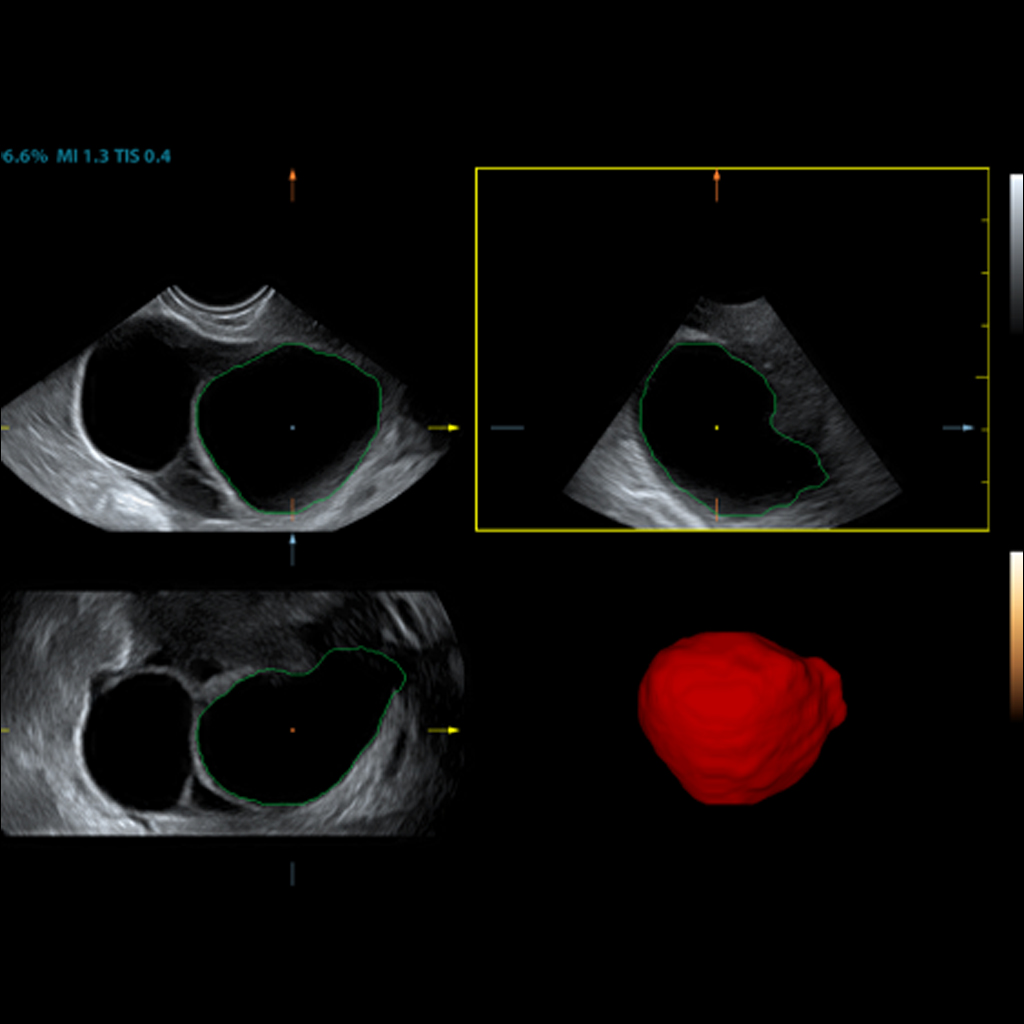

Помага за автоматично проследяване на неправилна тъканна граница с по-малко отклонение.